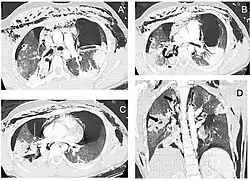

Paciente com ruptura completa traumática do brônquio direito. Tomografia computadorizada após drenagem torácica de emergência. Seções axiais de 1,25 mm com janela pulmonar. (a) Pneumotórax bilateral persistente, pneumomediastino e enfisema subcutâneo extenso. (b) Múltiplas lucências ao redor da árvore brônquica direita (seta curva) dificultando o reconhecimento da ruptura brônquica. (c) Efeito Macklin ao redor da veia pulmonar inferior direita (seta branca). (d) Vista coronal mostrando áreas de consolidação alveolar nos lobos superior e inferior direitos: lucências intraparenquimatosas resultantes de lacerações pulmonares são visíveis à direita (setas grossas).

O diagnóstico rápido e o tratamento são essenciais no cuidado da lesão traqueobrônquica;[6] se a lesão não for diagnosticada logo após o trauma, o risco de complicações aumenta.[11] A broncoscopia é o método mais eficaz para diagnosticar, localizar e determinar a gravidade da lesão,[6][10] sendo geralmente o único que permite um diagnóstico definitivo.[23] O diagnóstico com broncoscópio flexível, que permite visualizar diretamente a lesão, é a técnica mais rápida e confiável.[8] Na lesão traqueobrônquica, a broncoscopia pode revelar rasgo na via aérea, obstrução por sangue ou colapso de um brônquio, obscurecendo brônquios mais distais.[3]

A radiografia de tórax é a técnica inicial de imagem usada para diagnosticar a lesão traqueobrônquica.[17] A imagem pode não mostrar sinais em pacientes assintomáticos.[15] Indicações de lesão traqueobrônquica em radiografias incluem deformidade na traqueia ou defeito na parede traqueal.[17] Radiografias também podem mostrar enfisema cervical, ar nos tecidos do pescoço.[2] Raios X podem revelar lesões associadas e sinais como fraturas e enfisema subcutâneo.[2] Se o enfisema subcutâneo ocorre e o osso hioide aparece em uma radiografia posicionado anormalmente alto na garganta, pode indicar que a traqueia foi seccionada.[4] A lesão traqueobrônquica também é suspeita se um tubo traqueal aparece deslocado em uma radiografia, ou se seu balonete parece mais cheio que o normal ou protrai através de um rasgo na via aérea.[17] Se um brônquio é completamente rasgado, o pulmão pode colapsar para fora, em direção à parede torácica (em vez de para dentro, como no pneumotórax usual), pois perde a fixação ao brônquio que o mantém centralizado.[6] Em uma pessoa deitada de costas, o pulmão colapsa em direção ao diafragma e às costas.[23] Esse sinal, descrito em 1969, chamado sinal do pulmão caído, é patognomônico [en] da lesão traqueobrônquica (diagnóstico exclusivo, pois não ocorre em outras condições); no entanto, é raro.[6] Em até um em cinco casos de trauma contuso com lesão traqueobrônquica, não há sinais na radiografia torácica.[23] A tomografia computadorizada detecta mais de 90% das lesões traqueobrônquicas por trauma contuso,[3] mas nem raios X nem tomografia substituem a broncoscopia.[6]